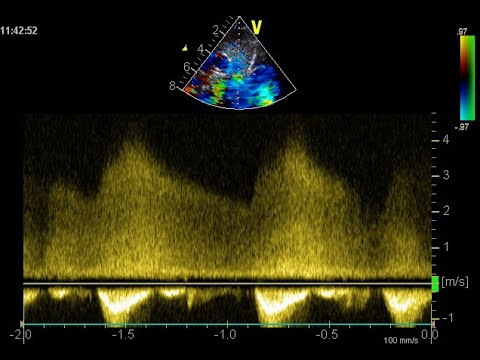

1er, 2ème avec des variantes, 3ème degré. Les blocs atrio-ventriculaires sont les déclinaisons d’une conduction variable. Évolutifs ou résolument complets, leurs variations imposent des actions plurielles en fonction de l’âge, des circonstances et du contexte de leur survenue. Comment les dépister, les surveiller, les appareiller sont autant de questions que de débats.